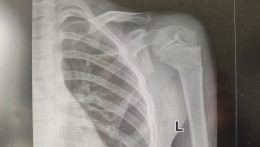

【微创骨科•新突破】攻“肩”克难,再创首例——我院成功开展首例半肩关节置换术!

时间:2024-09-07近日,日照市康复医院骨科团队完成首例难度大、要求高的半肩关节置换术!患者术后肩关节屈伸活动良好,疼痛消失,目前正在稳步康复中,这标志着我院在人工髋关节置换、膝关节置换等手术日益完善的基础上的又一次重大...

近日,日照市康复医院骨科团队完成首例难度大、要求高的半肩关节置换术!患者术后肩关节屈伸活动良好,疼痛消失,目前正在稳步康复中,这标志着我院在人工髋关节置换、膝关节置换等手术日益完善的基础上的又一次重大...